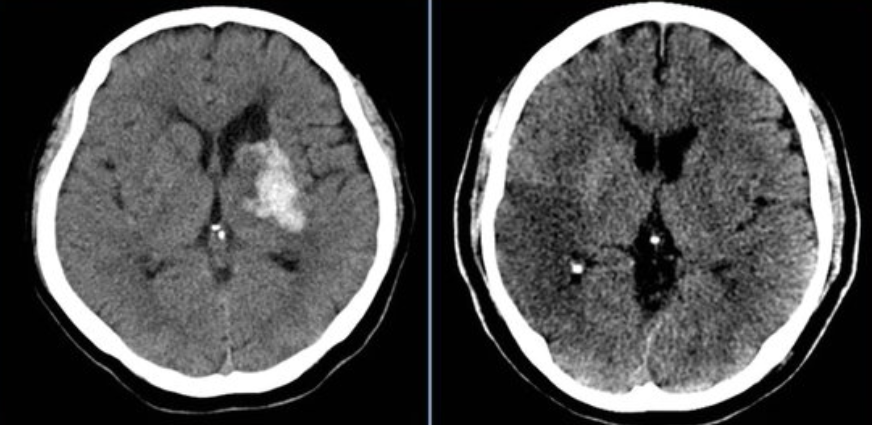

뇌출혈이나 매우 빨리 자라는 악성 뇌종양에 의한 급성 수두증은 급격한 뇌압 상승을 동반하는 매우 위험한 상황으로, 심한 두통, 구토가 나타나고, 의식저하, 팔다리 강직을 보이고 강직성 발작(hydrocephalic fit)을 보이기도 해서 빠른 치료를 요하게 됩니다.

뇌실이 급격히 확장하게 되면 두통, 오심, 구토, 시신경 유두 부종, 졸림, 코마 등의 증상을 보일 수 있고, 압력이 증가한 부위가 인접 부위 뇌를 밀어서 뇌간에 압력을 가하는 위험한 상황이 벌어질 수도 있습니다.